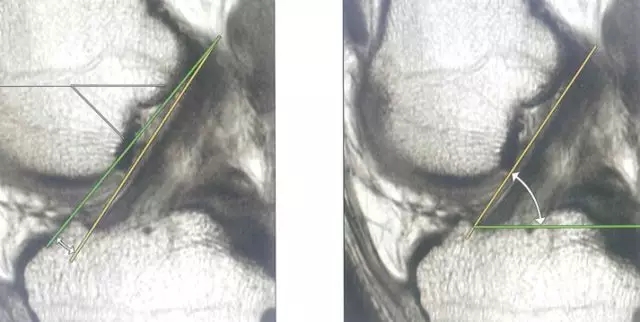

Blumensaat 角(-1.6度)

大于9-15度视为异常

前交叉韧带与胫骨平台角度(56度)

小于45-50度视为异常

后交叉韧带折弯度

弧度:0.19厘米,角度:114-123度